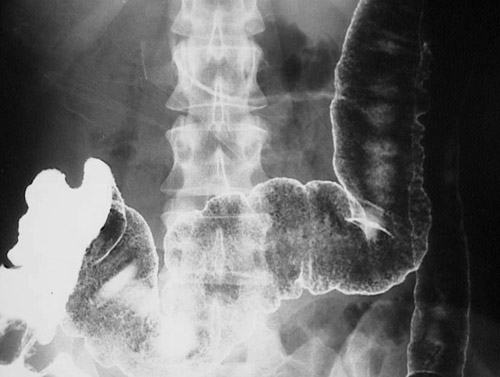

Image 1.3 On closer inspection, grossly the mucosa is completely eroded away, except for reddish "pseudopolyps". The radiographic view below is from a barium enema (not typically performed nowadays when colonoscopy can define the location of lesions and provide opportunity for biopsy) that reveals a coarsely granular mucosal pattern. |